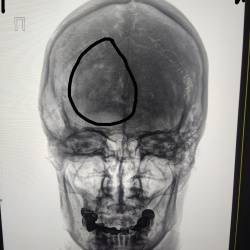

Мальчик, 2021 года рождения. Поступил в больницу по скорой помощи. Обстоятельства не известны. В дальнейшем переведен в детскую областную. Огнстрельное ранение черепа, из травматического пистолета...